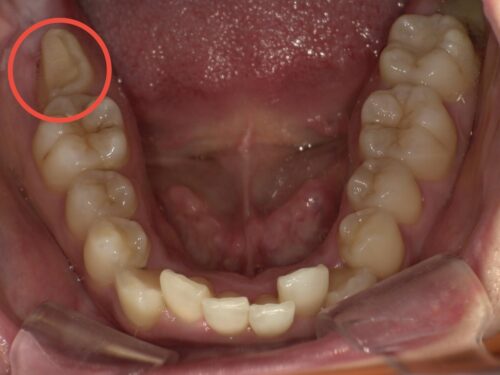

その2日後です。赤い円で囲んでいるのが抜歯予定の歯です。

赤い円で囲まれた部分に上顎の親知らずが存在していることが確認できます。

レントゲン写真で示されている上顎の親知らずを抜歯し、移植しました。

上顎にあった親知らずが下顎の奥歯の位置にあることがわかります。